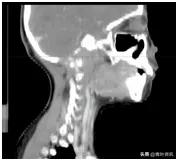

这可把珊珊爸爸妈妈急坏了,辗转多家大医院,颈部核磁共振检查发现颈椎、枕骨骨质广泛破坏、周边软组织形成(图一),后经病理检查确诊为朗格汉斯细胞增多症,是一种良性病!

图一 治疗前CT